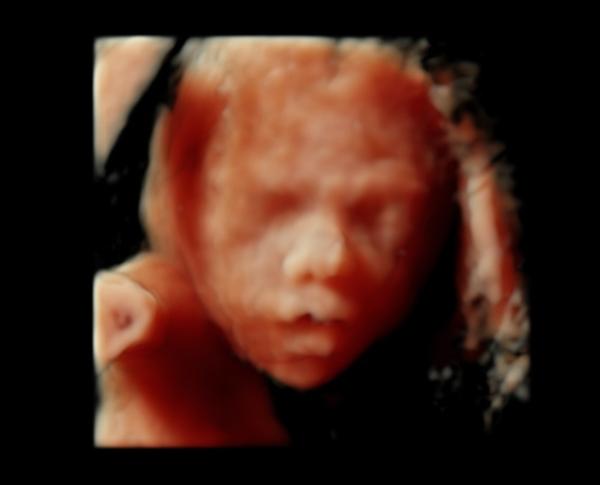

Zo 4D sa fotka nedá urobiť, lebo 4D ti ukazuje reálne v danej chvíli babatko. Iba 3D, tak mi to vysvetlila lekárka, ale v podstate je to to isté. Mne robila 3D, aj 4D potrápila sa, orezávala, lebo malá sa nechcela ukázať, ale máme krásnu fotku, malú sme videli krásne, detaily celej tváričky, celé telíčko. Je to nádherný obraz, bolo to krajšie ako som si dokázala predstaviť. Celé sono som preplakala 🙂 pravdupovediac na tej fotke ja osobne nevidím nič. Mám pocit, že moja lekárka robí krajšie fotky na normálnom sone. Za 3D sono som platila 30 eur.

4D znamena, ze vidis na UZV priamo pohyby babatka. kludne to mohlo byt 4D sono, ale fotku s pohybom ti nik nespravi, to by muselo byt video. cize fotka moze byt iba 3D alebo 2D. tvoja fotka vyzera ako 3D, pretoze je tam vidiet vypukliny do priestoru, takze sklamanie vyplyva iba z toho, ze si ocakavala kvalitnejsiu fotografiu... zrejme nemal lekar na to dostatocne dobry UZV, tieto pekne hnedo-ruzove fotky su este pocitacovo retusovane, aby vyzerali co najlepsie, na to treba fakt kvalitny pristroj... moj gynekolog v prvom tehotenstve mal tiez 4D sono a mam fotky porovnatelne s tvojou... pre mna vsak bolo skor dolezite vediet ze je maly v poriadku a fotim si ho teraz ked je medzi nami 🙂

Toto nie je 4D ale 3D. 4D = video. Z prvého tehotenstva mám asi 200 3D fotiek. Skutočne pekných. Podarili sa na prvý raz. Z druhého mám jednu, zozadu........ 🙄 bola som tam 4x jednoducho sa nedalo 😀 prírode nerozkážeš 😅 i keď je pravda že som za to neplatila aj napriek tomu že som tam strávila dosť veľa času.